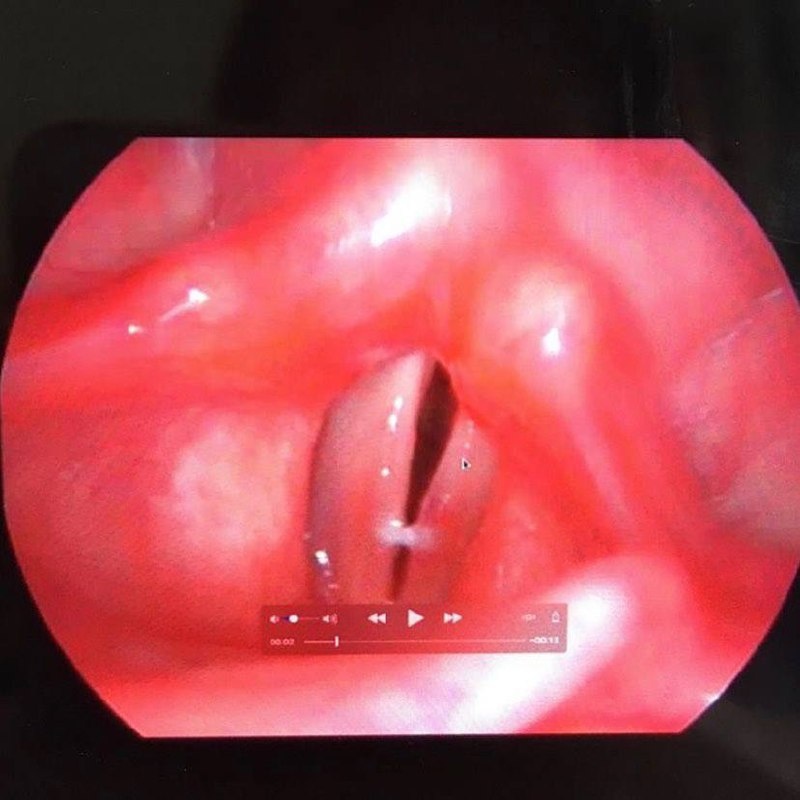

Что мы видим на ларингостробоскопии такое вкусненькое и интересненькое?